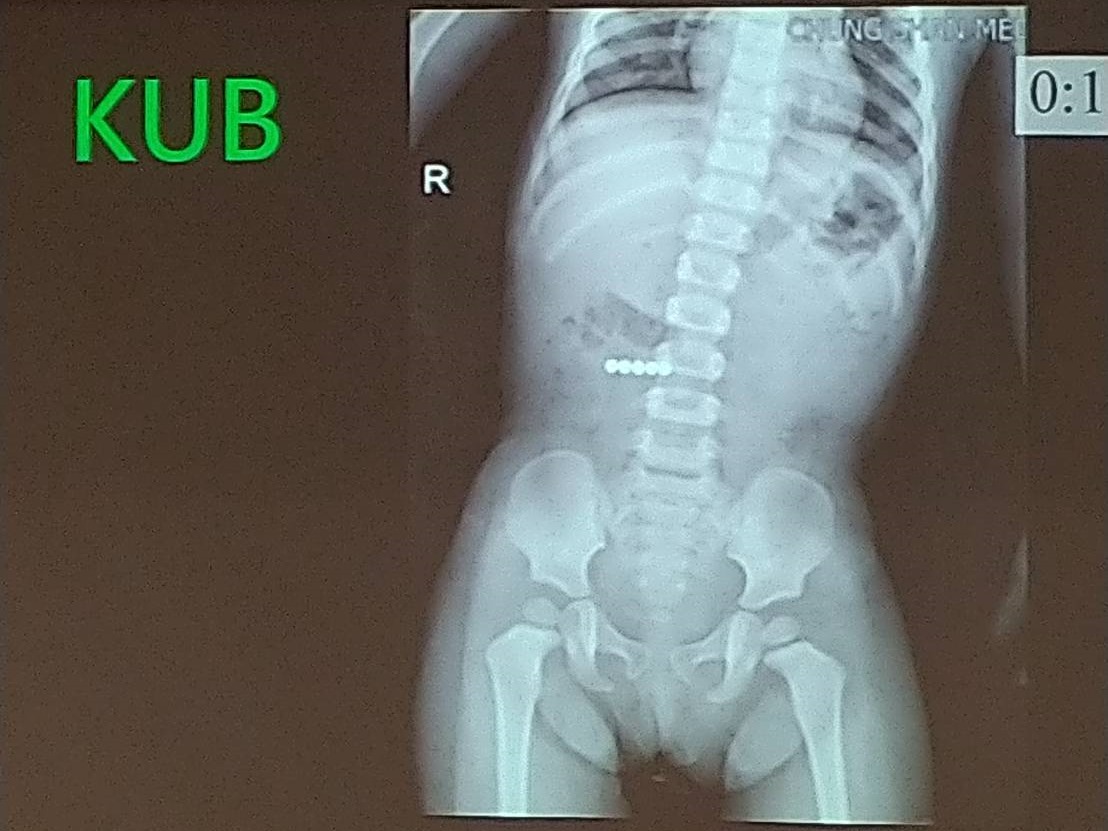

根据陆媒报导,中国一名10岁男童因身高只有110公分,被父母带至医院看诊,经医师检查后,发现男童的骨龄只有6岁,身形也比同年龄的孩子小许多。进一步诊断后,才发现影响男童的身高发育并非先天性因素,而是男童平时有「晚睡」及「开灯睡」的习惯。

经医师初步判断,应是男童平时习惯开灯睡,导致「褪黑激素」分泌过少,使得男童不易入睡,也难以进入深层睡眠,形成恶性循环,进而影响骨骼发育。